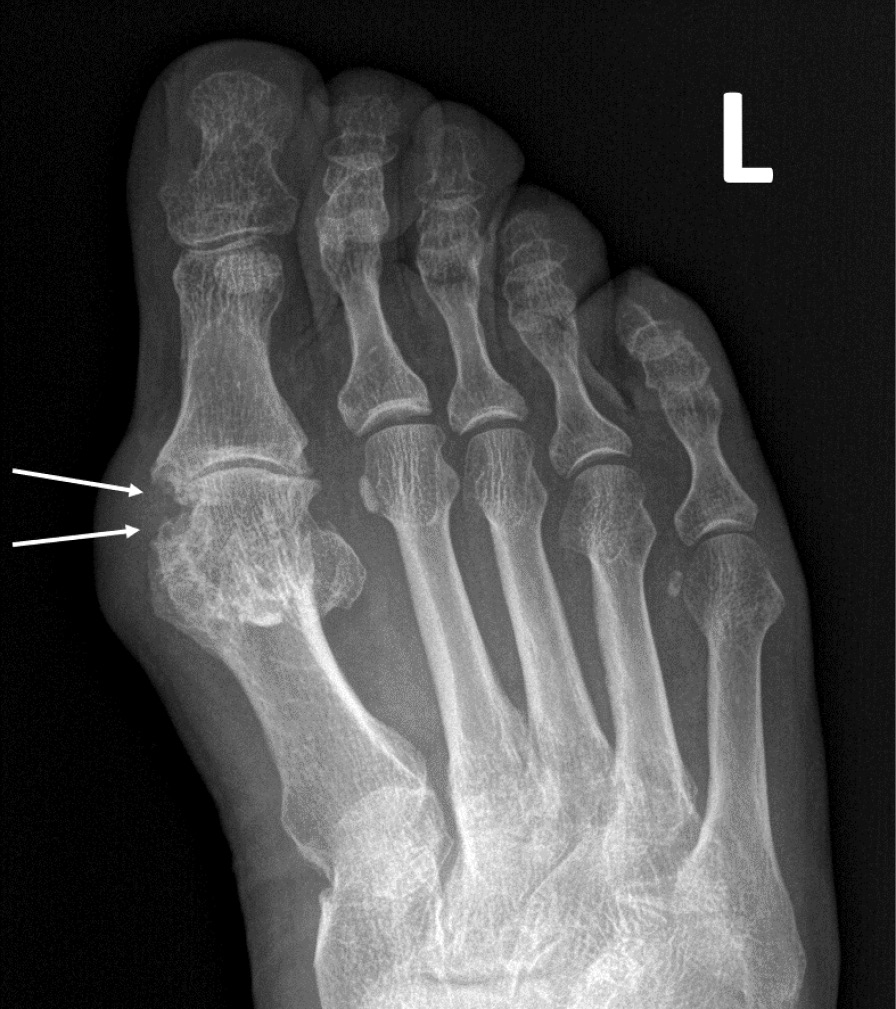

При компьютерной томографии органов грудной клетки данных за «свежие» очаговые и инфильтративные изменения не получено. Увеличения лимфатических узлов подмышечных областей, средостения, корней легких не выявлено. Отмечался усиленный грудной кифоз, обызвествление передней продольной связки, на всем уровне исследования определялись передне-боковые спондилофиты, а также анкилоз большинства реберно-поперечных суставов. По данным рентгенографии кистей (рис. 1, 2) и стоп (рис. 3, 4) диагностированы признаки эрозивного артрита, анкилоз суставов запястья. По данным МРТ крестцово-подвздошных суставов (КПС) определялся неравномерный анкилоз КПС, хрящи по суставным поверхностям неравномерной толщины, примерно на половине протяжении сустава отсутствуют, «суставной промежуток» облитерирован. Неравномерность и нечеткость контура суставных поверхностей за счет множества краевых эрозий справа, единичных – слева, с наличием остеокластоза, в нижнем отделе слева по смежным отделам определяются участки трабекулярного отека, данная находка клинически интерпретирована как двусторонний активный сакроилиит (рис. 5, 6).

Рис. 4. Рентгенограмма левой стопы в прямой проекции. Краевые эрозии суставных поверхностей первого плюсне-фалангового сустава (стрелки), сужение суставной щели. Вальгусная деформация I пальца стопы

В возрасте 40 лет присоединились жалобы на симметричные воспалительные боли в лучезапястных суставах и мелких суставах кистей, резкое снижение объема движения в лучезапястных суставах. При осмотре пациента выявлено: число болезненных суставов – 7, число припухших суставов – 4, положительный симптом поперечного сжатия кистей и стоп, ульнарная девиация мелких суставов стоп. Резко сниженный объем движения в лучезапястных суставах обеих кистей. По данным рентгенологического обследования зафиксированы типичные изменения для РА: резкое неравномерное выраженное сужение суставных щелей, субхондральный склероз в лучезапястных суставах, анкилоз в суставах запястья, пястно-запястных, пястно-фаланговых и межфаланговых суставах. Краевые эрозии оснований основных фаланг двух пальцев; участки кистовидной перестройки костной ткани. Локальное утолщение мягких тканей. При лабораторном обследовании пациента отмечен положительный ревматоидный фактор, высокий титр антицитруллинированных антител, повышение острофазовых белков.